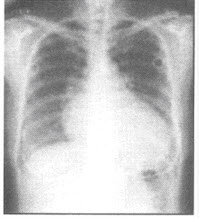

21、单项选择题

男,74岁,咳嗽,咳痰1月余,咯血丝痰1周伴胸痛,胸片如图,最可能的诊断为()

A.右上肺浸润型肺结核

B.右上肺不张

C.右侧中央型肺癌并右上肺不张

D.右侧包裹性积液

E.右肺上沟瘤